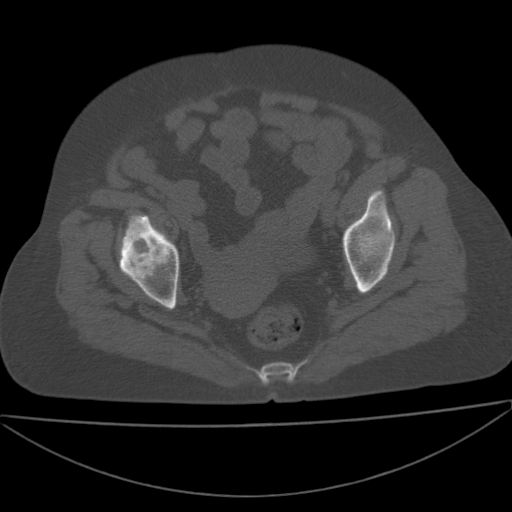

以下是引用余辉在2009-4-23 17:08:00的发言:[br]考虑右髋关节退行性变.股骨颈改变考虑陈旧性骨折可能,股骨头顶部关节面下似有透亮区,股骨头皮质环增厚,考虑有股骨头坏死

以下是引用王显瑞在2009-4-23 16:45:00的发言:[br]考虑股骨颈陈旧性骨折,股骨头缺血型坏死